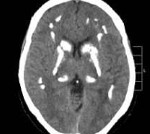

Но самый действенный способ диагностики – это компьютерная томография (КТ). На снимках КТ отчетливо видны участки с кальциевыми отложениями.

На снимке справа пораженный мозг

Основным инструментом в диагностике нейродегенеративной болезни можно назвать компьютерную и магниторезонансную томографию. На большинстве снимков видны конкретные участки поражения, что при рентгенограммах черепа было выявить затруднительно. Подтверждением диагноза является определение качественного содержания в плазме крови паратгормона и тиреокальцитонина.

На фото МРТ с дегенерацией мозга при болезни Фара

Болезнь Фара — идиопатическая симметричная кальцификация церебральных структур: подкорковых ганглиев, коры полушарий, мозжечка. Может протекать бессимптомно, клинически проявляется экстрапирамидными расстройствами (гиперкинезами, паркинсонизмом), мозжечковыми нарушениями, интеллектуальным снижением. Диагностируется по данным церебральной КТ при исключении вторичного характера кальцинированных очагов по результатам биохимических, ультразвуковых, ПЦР исследований. Лечение симптоматическое с применением средств, улучшающих тканевый обмен, цитопротекторов, препаратов леводопы, антиконвульсантов.

Основным диагностическим методом, позволяющим неврологу достоверно установить наличие очагов кальциноза в мозговых тканях, является КТ головного мозга. Интенсивность очагов на томограммах отражает уровень концентрации кальция. МРТ головного мозга значительно хуже визуализирует кальцификаты, но позволяет оценить сопутствующие дегенеративные процессы. С целью подтверждения идиопатического характера патологии проводится целый ряд дополнительных обследований: